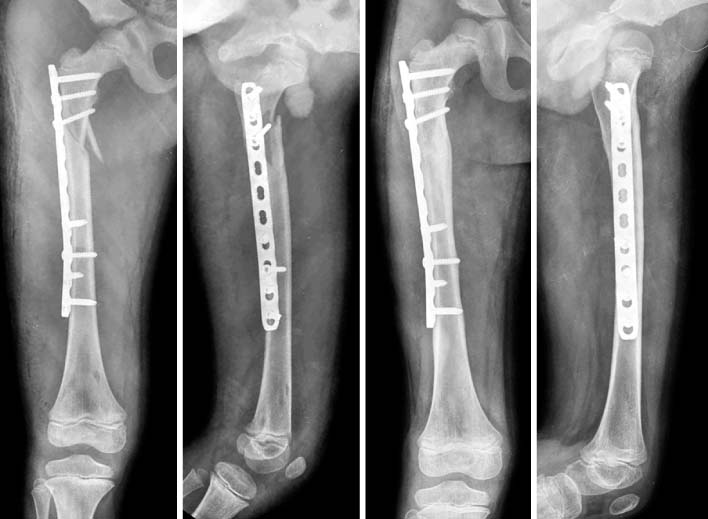

Fig. 1

A femoral shaft fracture with a butterfly fragment in 11 years-old girl.

Fig. 6

In postoperative films (left), a satisfactory reduction was achieved. The patient had a solid union, on 1 year follow-up films (right).